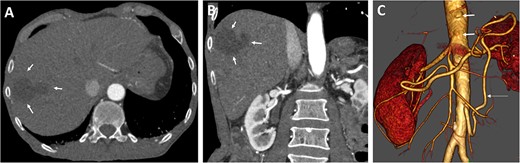

Postoperative axial (A) and coronal (B) CT angiographic images demonstrate enhancement during contrast-enhanced phase and hepatic ischemic area with irregular margins. (C) 3D reconstructed CT angiography shows antegrade visceral reconstruction with a bifurcated graft from the supra-celiac aortic donor to the superior mesenteric and celiac arteries (arrows).